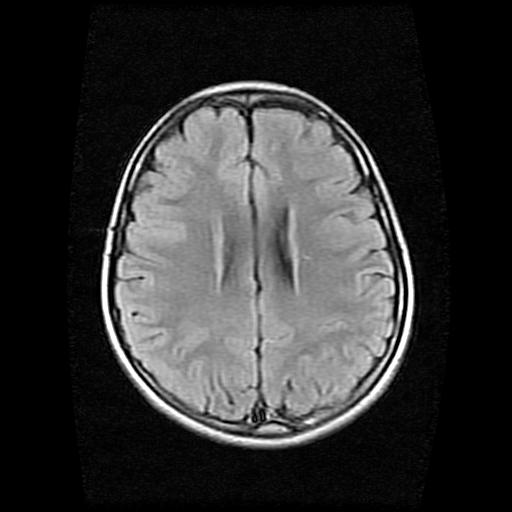

9岁女孩,三岁时诊断为癫痫,一直服丙戊酸钠,现患者一般情况良好,家长复查核磁片,看能否停药..

巨脑回

未见异常信号灶.

未发现异常信号。